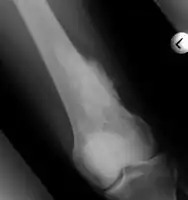

Medical imaging usually shows a well-defined wide-based bony growth on the surface of bone.[5] It can be pedunculated and irregular, giving it a "bizarre" appearance, and is not connected to underlying bone.[2]

X-ray hand, BPOP 2nd metacarpal

X-ray hand, BPOP 2nd metacarpal (side view)